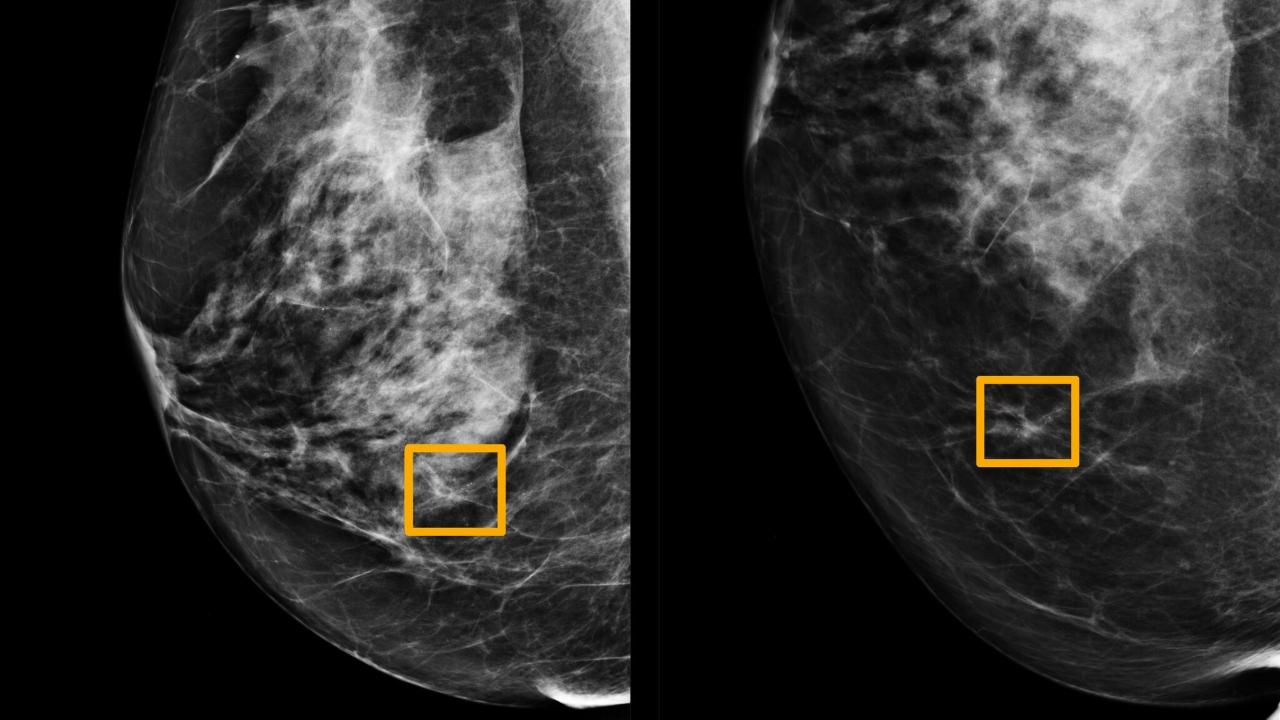

Žlté políčko na obrázku označuje, kde systém AI zistil, že rakovina sa skrýva vo vnútri prsného tkaniva. Šesť predchádzajúcich rádiológov nedokázalo nájsť rakovinu v rutinných mamografických vyšetreniach.